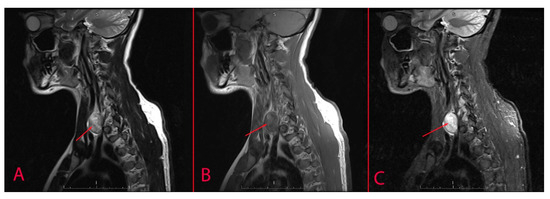

| MRI | Schwannoma | Solid low-intensified and high-intensified tumour by T1- and T2-weighted images, respectively; can be connected to the cervical spinal cord. MRI can delineate mass as distinct from less hyperintense thyroid and enhanced T1-weighted images and demonstrate plane of separation between lesion and thyroid gland. | |